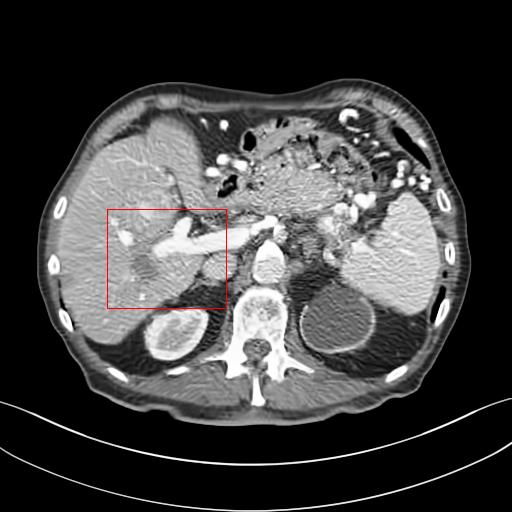

Figure 3: Comparison of denoising performance of different network. The boundary line of different organ extracted from the NDCT image is superimposed on other images. As seen, many pixels are missing around the boundary line in the output of M1

Figure 4: Zoomed version of the ROI taken from the images of Figure 3. In the zoomed version missing boundary pixel is clearly visible in the output of M1.

This section systemically investigates the efficacy of every module proposed in this study. We considered three different networks; first, baseline model(M1), where the inverting block is replaced with dense block, and trained using minimizing mean square distance between two noisy observations(i.e. fsubscript𝑓\mathcal{L}_{f}). Next, two independent baseline model(one for forward mapping, one for reverse mapping) is jointly trained using a linear combination fsubscript𝑓\mathcal{L}_{f}, and rsubscript𝑟\mathcal{L}_{r}, similar to cycle consistent network paradigm. The forward mapping network is used for testing. We refer this model as M2. In both M1, and M2, we increased the depth of the network to make the representation power of these networks comparable with inverting network. Finally, the proposed method, referred as M3. Table 2 depicts the objective evaluation of the three networks using the D1 dataset. Both M2 and M3 use reverse mapping to regularize the network; the influence of the same in the denoising performance is evident from Table 2. Adding cycle consistency loss has improved the performance of the same baseline model significantly. The inverting network performed considerably better than the network M2. It improves PSNR by 0.23dB. As discussed in the above section, in case cycle consistency loss, an additional network is trained, but that does not always guarantee invertibility, whereas inverting network architecture inherently possesses reversibility, which acts as a strong regularizer. In Figure 3 we have shown denoising performance of different networks visually. To demonstrate the requirement of regularization, we first extract the boundary line of the various organ from the NDCT image and superimpose the boundary line on the output of different networks. As shown in Figure 3, many pixels around the boundary line of M1 network output are missing. Using the reverse mapping, the issue of the end-organ missing pixel is successfully overcome in M2 and M3. The granular pattern is also less present in the M3 than M2. The zoomed version of a ROI taken from the images of Figure 3 is given in Figure 4 for better perception. In Figure 5 we give an example of the performance of the invertible network in reverse mapping. Here, the predicted LDCT image is produced by using the predicted clean image of the forward mapping as the input for reverse mapping. As shown, the predicted noisy pattern is similar to the original noise pattern. The same streaking artifacts are present in both the noise pattern; also, the noise variance is different in the various spatial region depending on the signal intensity of the original CT image. It validates that the loss of information in reverse mapping is minimal. Due to the invertible network’s structural advantage, the network also preserves every information present in the input image in the forward mapping.